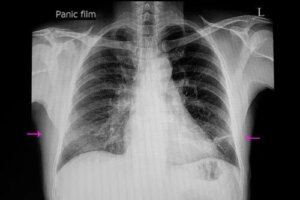

Pentru diagnosticarea atelectaziei, o explorare clinică adecvată și o radiografie sunt suficiente. În plus, medicii pot folosi o serie de tehnici pentru a confirma diagnosticul sau pentru a determina gradul de severitate a bolii.